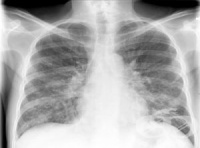

При нас възрастните има голяма вероятност острият бронхит да се превърне в хроничен, поради рисковит...